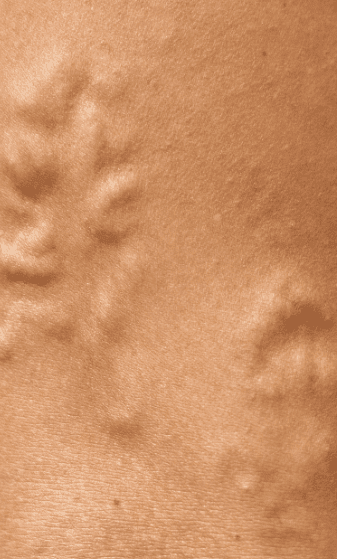

A varicose vein is one that’s become abnormally dilated due to pressure accumulating in the vein. Venous valves direct blood in a singular direction by closing once blood passes through. When valves fail, blood collects in the vein and causes the bulging bluish vessels you see beneath your skin.

While some spider veins run in a straight line, most appear in spindly clusters resembling a spider’s web, hence the name. These small telangiectasias appear on the legs or face, and are red, blue, or purple.

Spider veins often form as a result of venous reflux, or the backward flow of blood through your veins. If a one-way valve within your vein malfunctions, blood collects, imposing internal pressure on the vein. This forces new spider veins to branch out from the vein. You might not notice symptoms with spider veins, but some patients experience pain, cramping, heaviness, swelling, or itching. Our CT vein treatment team identifies the underlying issue to resolve these unhealthy veins.